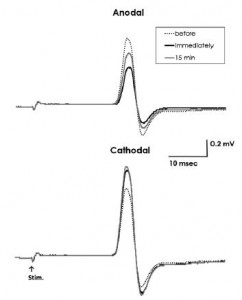

Sasaki R, Miyaguchi S, Kotan S, Kojima S, Kirimoto H, Onishi H. Modulation of cortical inhibitory circuits after cathodal transcranial direct current stimulation over the primary motor cortex. Frontiers in Human Neuroscience. 2016; doi: 10.3389/fnhum.2016.00030.